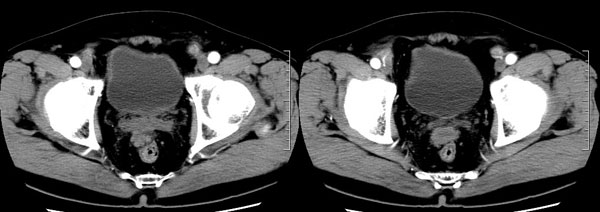

| 男性,69岁。自2个月前开始无意中发现左侧阴囊内一鸡蛋大小肿物,当时无伴疼痛等不适,未予重视。肿物逐渐增大,近段时间常伴左会阴部、腹股沟区牵扯不适,并于2周前在我院门诊行彩超检查提示“左侧附睾肿瘤可能,左侧睾丸鞘膜积液”。 专科检查:左侧阴囊肿大,其内可触及一鹅蛋大小肿物,表面光滑。肿物前部呈囊性感,后部质硬,按压无疼痛,无缩小,活动度良好。左侧睾丸未触及,透光试验(±)。                 王仕学发言:左侧睾丸见一密度不均肿块,边缘清楚,周围见水样密度影;考虑睾丸生殖细胞性肿瘤可能性大. 睾丸肿瘤占生殖系统肿瘤的3%-5%,占男性恶性肿瘤的0.5%-1.0%,其中生殖细胞性肿瘤占95%.睾丸肿瘤包括生殖细胞和非生殖细胞肿瘤两大类,前者占95%以上,后者不到5%.非生殖细胞肿瘤虽少见,但种类繁杂,主要有支持细胞、间质细胞和支持细胞-间质细胞瘤等功能性肿瘤,和间皮瘤、腺癌、横纹肌肉瘤、粘液性囊腺瘤、纤维上皮瘤、黑素神经外胚瘤、淋巴瘤等附属组织肿瘤。不同的病理类型的睾丸肿瘤发病率高峰不同,睾丸癌多发于35岁以前,精原细胞瘤发病高峰为30-35岁。精原细胞瘤约占睾丸肿瘤的60%,发病高峰在30-35岁。85%的患者睾丸有明显肿大,肿瘤局部侵犯力较低,肿瘤一般有明显界限。 手术:行“左侧附睾、睾丸、精索切除术”。 病理诊断:(左睾丸、附睾)肿物,为低分化腺癌。另送检(左精索远端)肿物,镜下亦为低分化腺癌。 免疫组化:ck(l)(++++)、cea(+++)、ca19-9(-)、psa(-)、plap(-)、p53(-)、vimentin(-)。 原贴地址:http://www.radinet.com.cn/forum_view.asp?forum_id=4&view_id=30707 |